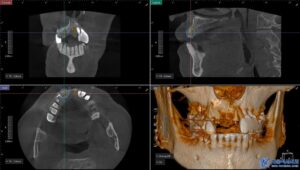

무절개 임플란트는 컴퓨터 분석을 통해

미리 계획된 경로를 따라 식립하기 때문에

절개가 필요하지 않고 출혈이 적으며

회복 속도가 빠릅니다.

또한, 위 사진처럼

수술가이드를 제작하여 오차 없이

정밀한 위치에 임플란트를

심을 수 있기 때문에

성공률도 높아지게 됩니다.